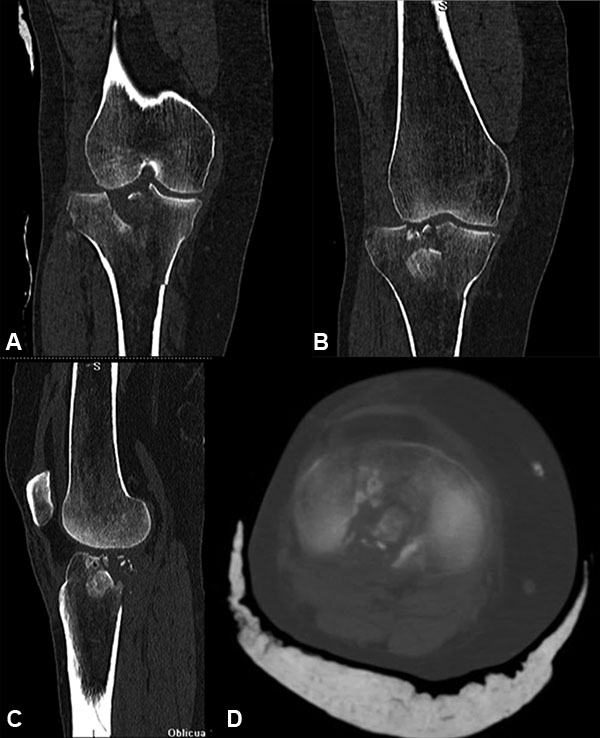

El diagnóstico se realizó siguiendo los hallazgos clínicos, radiográficos, de la tomografía computada o la RMN según el caso (figs. 1 a 7).

Figura 4: Masculino 58 años. Schatzker V.

Figura 5: Masculino 58 años. Schatzker V.

Figura 6: Cortes tomográficos paciente anterior.